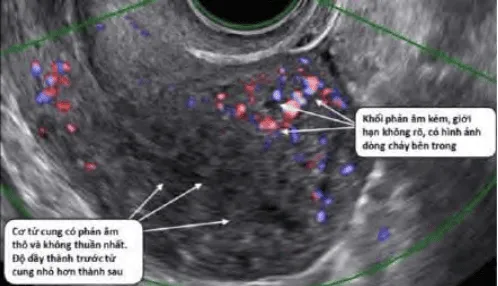

Phần tiêu đề “Cận lâm sàng”Siêu âm thang xám: Khối giảm âm, giới hạn rõ, bóng giảm âm sau.

Hình ảnh “U xơ tử cung trên siêu âm”.

Hình ảnh “Adenomyosis trên siêu âm”.

Hình ảnh “Leiomyosarcoma trên siêu âm”.

Doppler: Mạch ngoại vi u xơ; Phân biệt với polyp (mạch trung tâm) và adenomyosis (mạch nội vi).